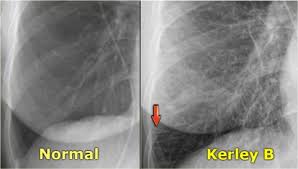

X Ray Imaging Can Be Used To Diagnose Whether A Patient Has Congestive Heart Failure Heart Failure Congestive Heart Failure Failure

The Radiology Assistant Heart Failure